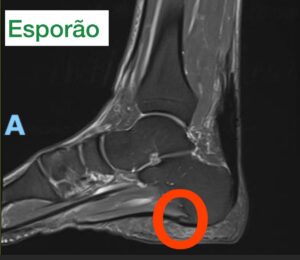

pé Fascite Plantar: Causas, Sintomas e Tratamentos Leia mais » abril 15, 2025 Geral 5 Fatos Essenciais Sobre a Panturrilha: Saúde, Função e Exercícios Leia mais » abril 15, 2025 joelho Artroscopia do Joelho Leia mais » março 27, 2025 Uncategorized Laser para joelho – Tratamento da Osteoartrite Leia mais » março 1, 2025 Geral Mialgia Tibial anterior: Não Confunda com Canelite: Leia mais » fevereiro 11, 2025 Uncategorized Fratura da Patela Leia mais » janeiro 29, 2025 Exercícios para Condromalácia nos Joelhos: Fortaleça com segurança Leia mais » janeiro 28, 2025 joelho Osgood-Schlatter: entendendo essa condição Leia mais » janeiro 27, 2025 Uncategorized Artrite Psoriática e inflamação articular Leia mais » janeiro 26, 2025 Tornozelo Torção do Tornozelo: Causas, Sintomas e Tratamentos Leia mais » janeiro 25, 2025 Tornozelo Tendinite Fibular: da causa ao tratamento Leia mais » janeiro 25, 2025 mão Síndrome do Túnel do Carpo Leia mais » janeiro 22, 2025 Geral Fêmur: O Maior e Mais Forte Osso do Corpo Leia mais » janeiro 16, 2025 Geral Tíbia: o principal osso da perna Leia mais » janeiro 16, 2025 Geral Luxação: O Que é, Causas, Sintomas e Tratamentos Leia mais » janeiro 7, 2025 Tornozelo Anatomia do Tornozelo: Ossos, Ligamentos e Tendões Leia mais » janeiro 3, 2025 Geral Clínica de Ortopedia em São Paulo Leia mais » dezembro 17, 2024 Uncategorized Dor Lateral no Joelho – 5 principais causas Leia mais » dezembro 17, 2024 Uncategorized Pubalgia: Causas, Sintomas e Tratamentos Leia mais » dezembro 16, 2024 Uncategorized Dor Atrás da Coxa: Principais Causas, Diagnóstico e Tratamento Leia mais » dezembro 13, 2024 Geral Bursite no Braço: Causas, Sintomas e Tratamento Leia mais » dezembro 11, 2024 Uncategorized Lombalgia Leia mais » dezembro 10, 2024 Uncategorized Cirurgia de Joanete: Quando Optar e Como Funciona Leia mais » dezembro 9, 2024 joelho Inflamação do Tendão Patelar: causas, sintomas e tratamento Leia mais » dezembro 6, 2024 joelho Bloqueio dos Nervos Geniculares no Joelho Leia mais » dezembro 3, 2024 joelho Hoffite: inflamação no joelho Leia mais » dezembro 2, 2024 joelho Dor no Joelho: as 15 principais causas Leia mais » dezembro 1, 2024 Geral Quadríceps: O Maior Grupo Muscular do Corpo Leia mais » novembro 27, 2024 Geral Panturrilha sentado e em pé Leia mais » novembro 27, 2024 joelho Cisto de Baker: Causas, Sintomas e Tratamentos Leia mais » novembro 18, 2024 Geral Osso: Estrutura, Funções e Saúde Leia mais » novembro 15, 2024 Ortopedia e Traumatologia Fratura Exposta: Entendendo as Fraturas Expostas de Fêmur e Tíbia Leia mais » novembro 15, 2024 Geral Canelite: Tudo o Que Você Precisa Saber Leia mais » novembro 11, 2024 joelho Infiltração no joelho Leia mais » novembro 11, 2024 coluna Nervo Ciático: tudo o que você precisa saber Leia mais » novembro 11, 2024 Geral Cãibras: Causas, Sintomas e Tratamentos Leia mais » novembro 10, 2024 Ortopedia e Traumatologia Especialista em Joelho Leia mais » novembro 5, 2024 Ortopedia e Traumatologia 4 bursites comuns: entenda e veja os tratamentos Leia mais » novembro 5, 2024 pé Metatarsalgia: dor na região anterior do pé Leia mais » outubro 30, 2024 Tornozelo Tornozelo Inchado: 7 Causas, Sintomas e Tratamentos Leia mais » outubro 28, 2024 Geral Mialgia: Causas, Sintomas e Tratamentos Leia mais » outubro 27, 2024 Geral Tendão de Aquiles: Função, Lesões e Tratamentos Leia mais » outubro 22, 2024 pé Anatomia dos Ossos do Pé: Estrutura e Função Leia mais » outubro 20, 2024 Ortopedia e Traumatologia Água no joelho (derrame articular) Leia mais » outubro 16, 2024 joelho O que é gonartrose ? Leia mais » outubro 16, 2024 cotovelo Epicondilite Lateral do Cotovelo: Causas, Sintomas e Tratamentos Leia mais » outubro 4, 2024 joelho Água no joelho (derrame articular) Leia mais » outubro 1, 2024 Geral Anti-inflamatórios: O Que São, Como Funcionam e Seus Usos na Ortopedia Leia mais » outubro 1, 2024 Geral O Que é Esporão: Causas, Sintomas, Diagnóstico e Tratamento Leia mais » outubro 1, 2024 quadril Bursite do Quadril: tudo o que você precisa saber Leia mais » setembro 18, 2024 Uncategorized O Que é Esporão no Pé? Causas, Sintomas e Tratamentos Leia mais » setembro 18, 2024 Geral Terapia por Ondas de Choque: O Que É, Como Funciona e Seus Benefícios Leia mais » setembro 17, 2024 joelho O que é gonartrose ? Leia mais » agosto 10, 2024 Geral Lesão Osteocondral: Diagnóstico, Tratamento e Reabilitação Leia mais » agosto 10, 2024 pé Dor no Pé: um queixa super frequente Leia mais » julho 13, 2024 joelho Problemas nos Joelhos: Causas, Sintomas e Tratamentos Leia mais » julho 7, 2024 Geral Ortopedia, entenda esta especialidade médica Leia mais » julho 5, 2024 joelho Joelho Estalando com dor, sem dor, é normal ? Leia mais » julho 5, 2024 BLOG – DICAS DE SAÚDE Leia mais » julho 2, 2024 Tornozelo Fratura por Estresse no Pé Leia mais » julho 1, 2024